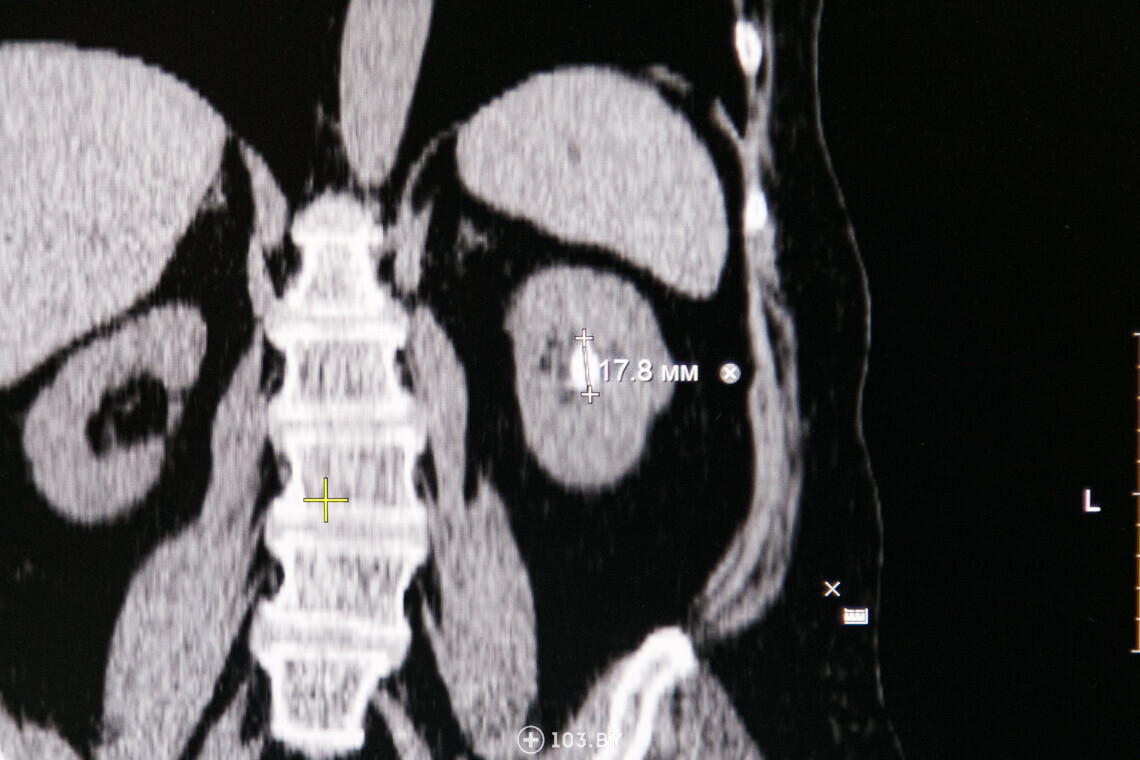

- ультразвуковое исследование;

- рентген органов мочевой системы, экскреторную урографию, компьютерную томографию.

Единой схемы лечения нет. Тактика зависит от состояния пациента, от места нахождения камня, от его плотности, размеров. Для эффективного лечения нужно комплексное применение современных эндоскопических и бесконтактных хирургических методов.

Мочекаменная болезнь может долго протекать бессимптомно. Если небольшой камень не нарушает отток мочи, находится в нижней или средней чашке почки, он может не беспокоить годами. Обычно конкремент обнаруживают на рентгенологическом или ультразвуковом исследовании. Боли появляются, когда камень вызывает нарушение оттока мочи из почки.